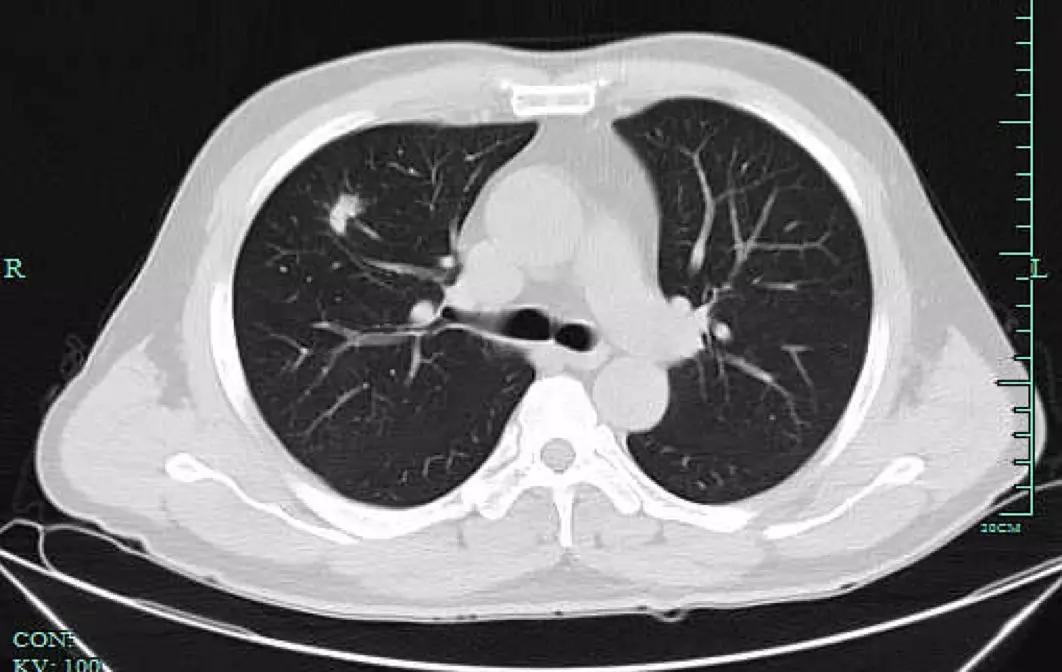

但也许是因为太拼了,章女士轻忽了自己的身体变化。前年7月,章女士开始咳嗽,“是那种干咳,也没有流鼻涕没有喉咙痛,应该不是感冒。”她回忆,因为咳得实在难受就想去社区医院配点药,但医生建议她最好去大医院检查一下。章女士便来到浙大一院就诊并预约了检查,拿到体检结果那一刻她却直冒汗,“CT结果说我两侧的肺上都有磨玻璃小结节,右肺上叶的已经有1厘米大了,首先考虑是肺癌,我吓都吓‘死’了。”

肺结节是肺癌筛查中最常发现的类圆形、密度增高的肺部阴影。如果从大小来看,直径小于5毫米的叫做微小结节,直径在5毫米至10毫米的叫做肺小结节,小于3厘米的为肺结节,而如果直径大于3厘米就是肿块了。

磨玻璃样结节

磨玻璃样结节是指肺内密度轻微增加,呈模糊的云雾状,但仍能通过病灶看到其内部血管和支气管纹理,就好像透过磨玻璃观察一样。

实性结节是指肺内圆形或类圆形高密度阴影,在CT下呈现白色的影子,足以掩盖它走行的血管和支气管。实性结节的良恶性较难鉴别,有时候很难光凭一张CT来判断,医生需要充分了解病人的既往病史,比如是否有过肺结核、肺炎、其他肿瘤性疾病等,必要的时候,可以通过PET-CT,肺穿刺,甚至微创手术切除等方式明确诊断。